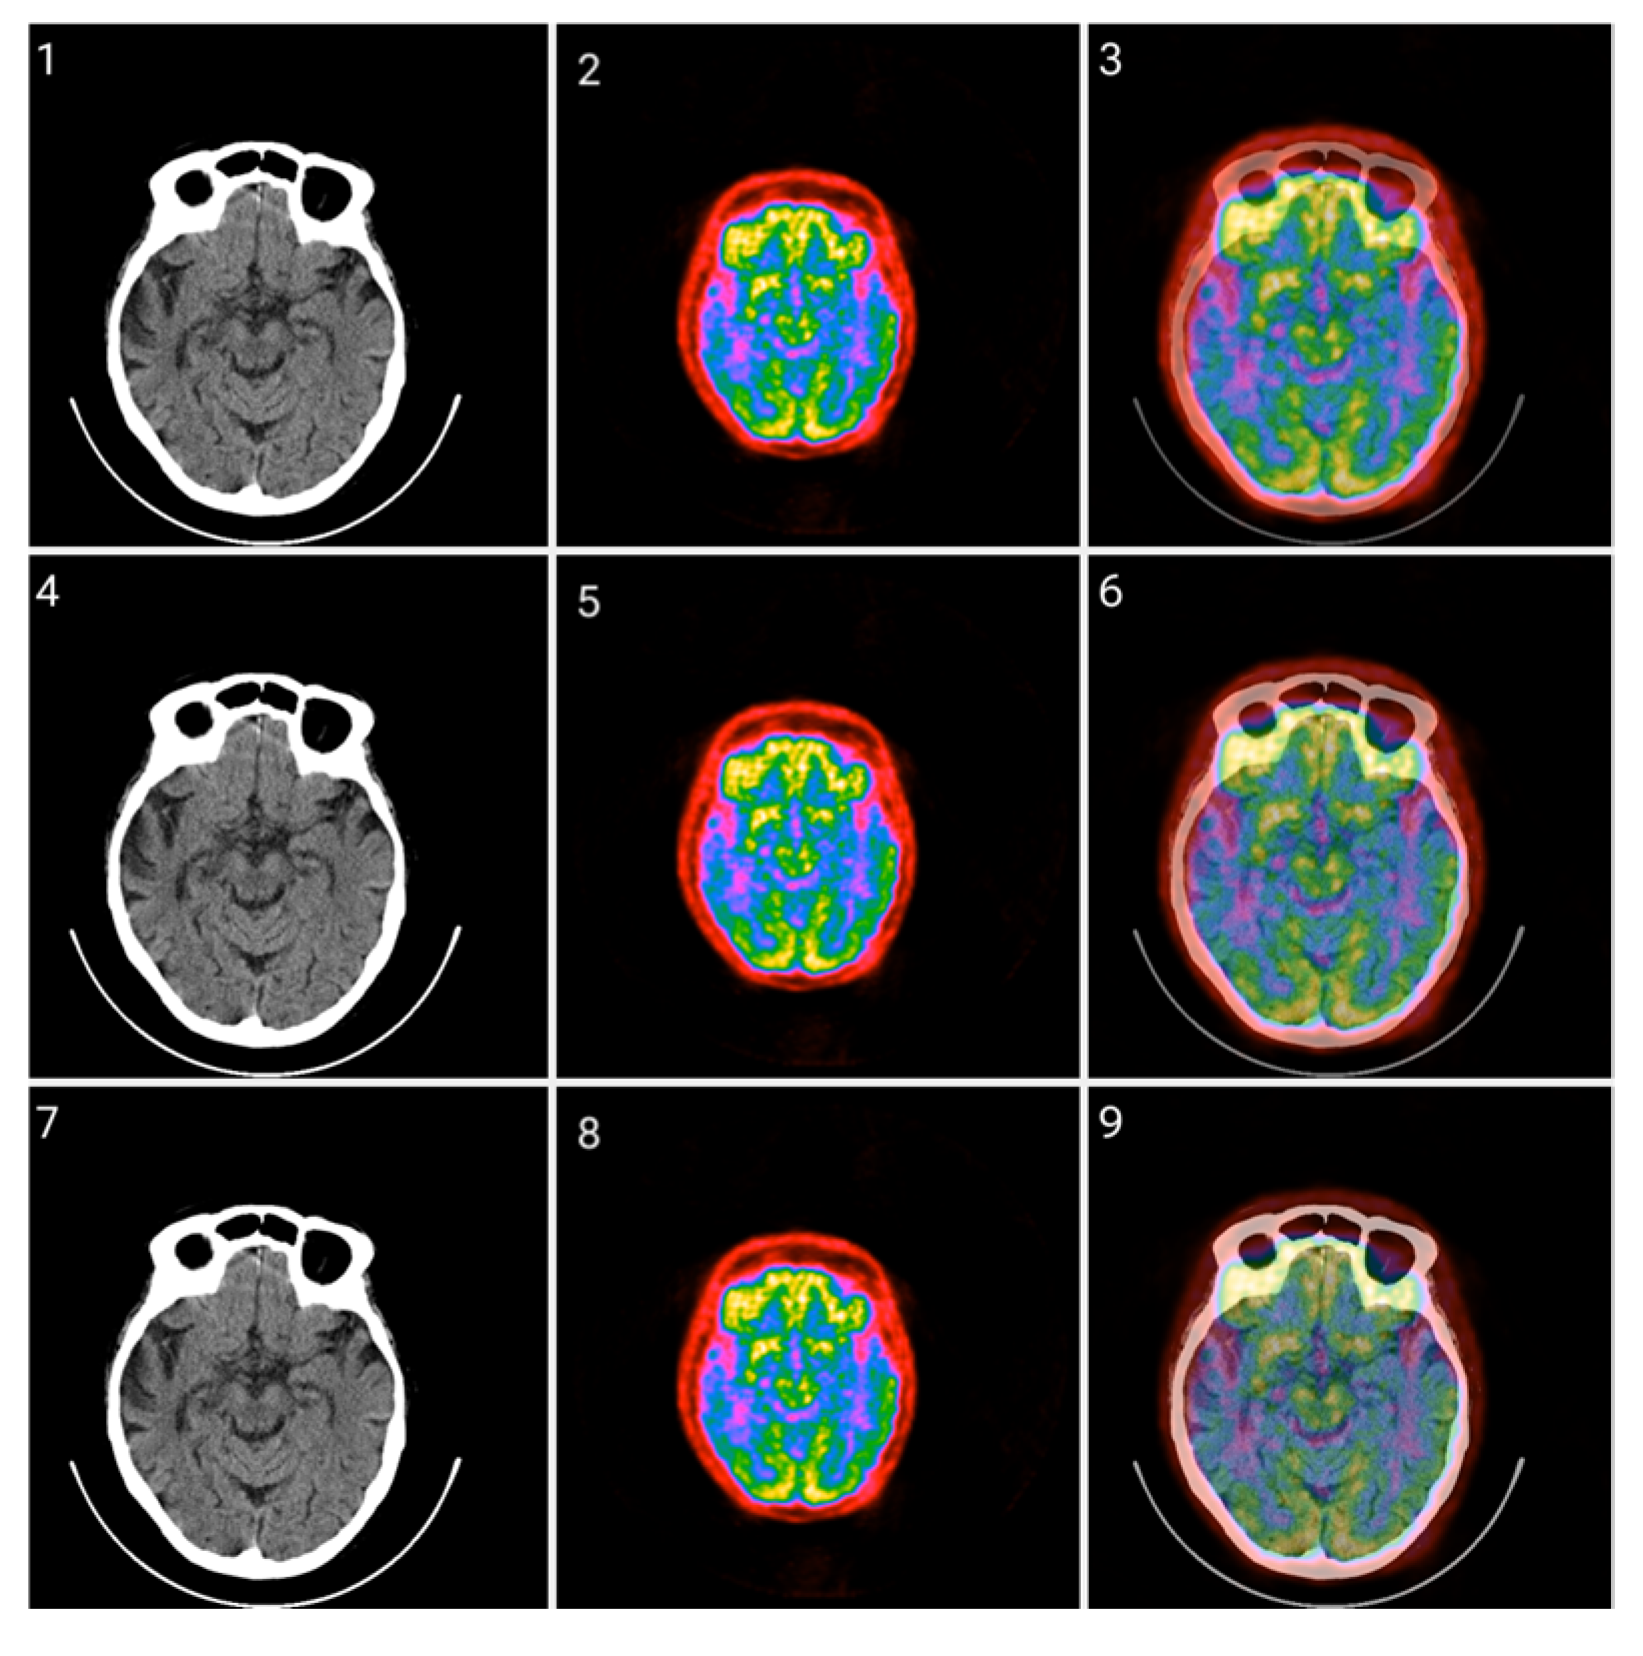

Figure 13.

Fusion of CT and PET images at different ratios. Images 1, 4, and 7 present a standard windowed CT image. Images 2, 5, and 8 present the corresponding PET image after Colormap Folding by 2 folds. Images 3, 6, and 9 present the results of fusing the CT and PET images at different ratios, 35%, 50%, 65% CT with 65%, 50%, 35% PET, respectively.